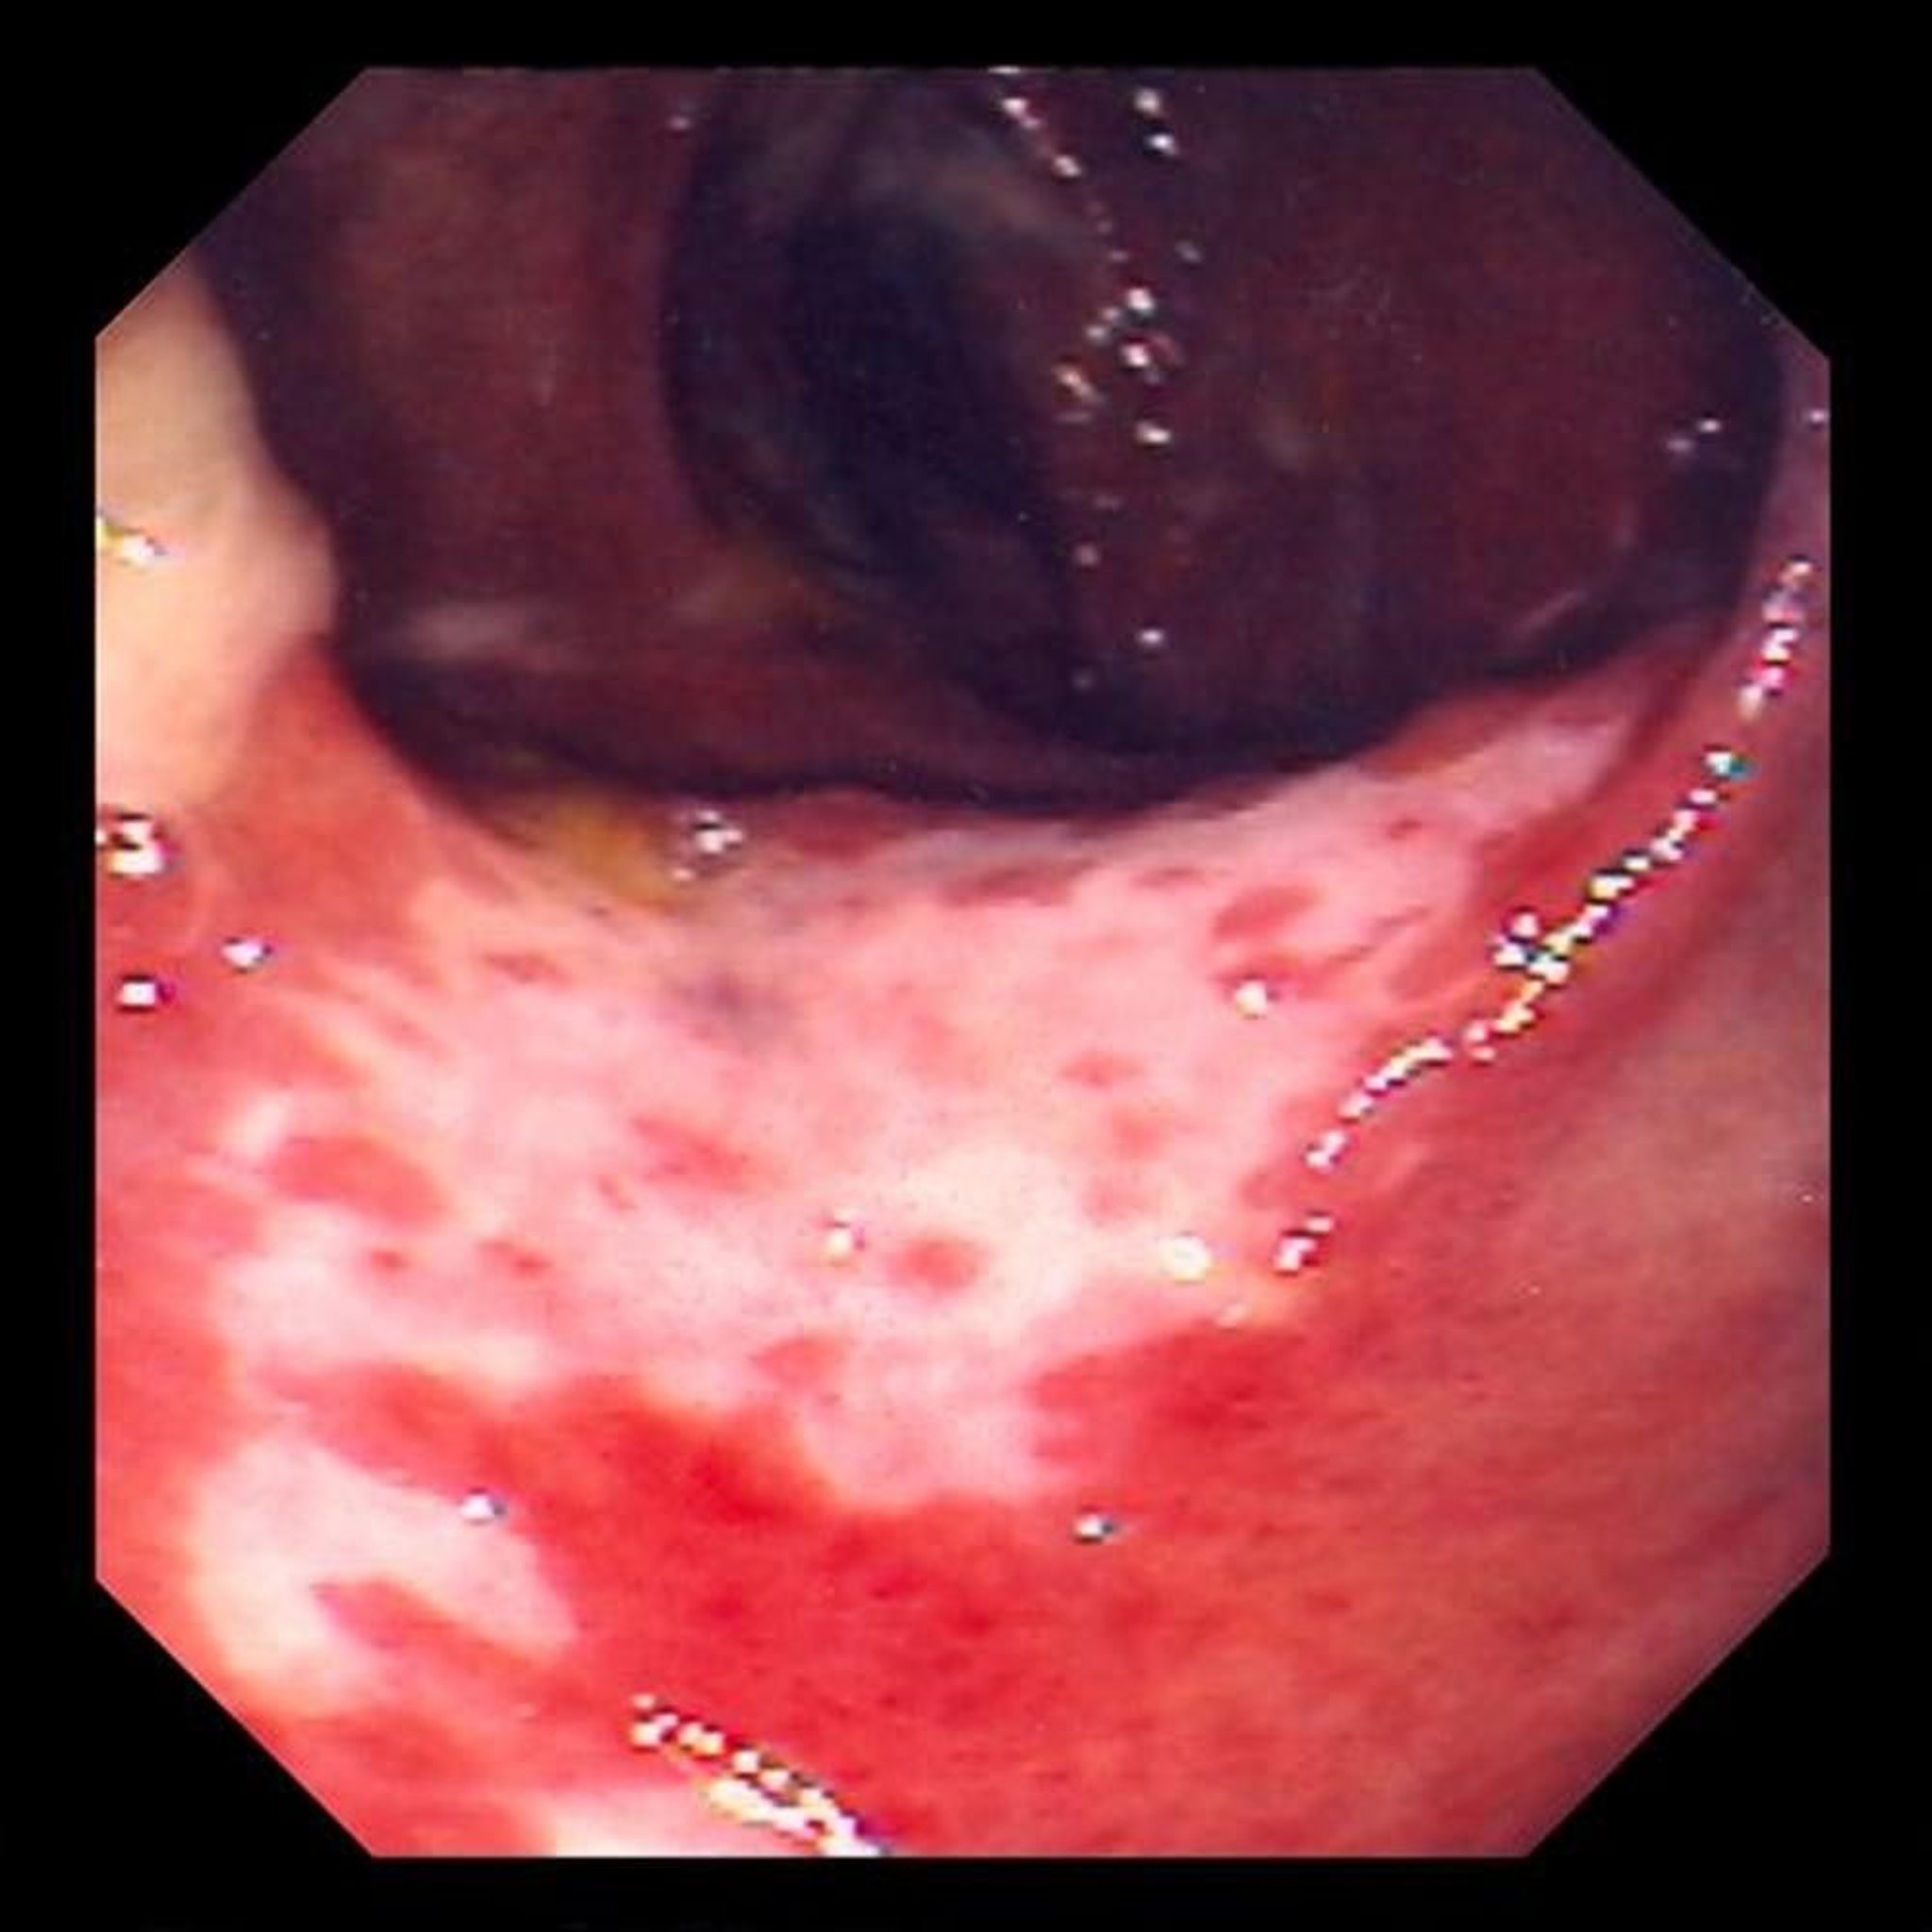

Ischemic Colitis (Colonoscopy)

This photo shows damage to the lining of the intestine caused by blockage of blood flow. The lining of the intestine is red and covered with ulcers (the white areas).

Photo provided by David M. Martin, MD.